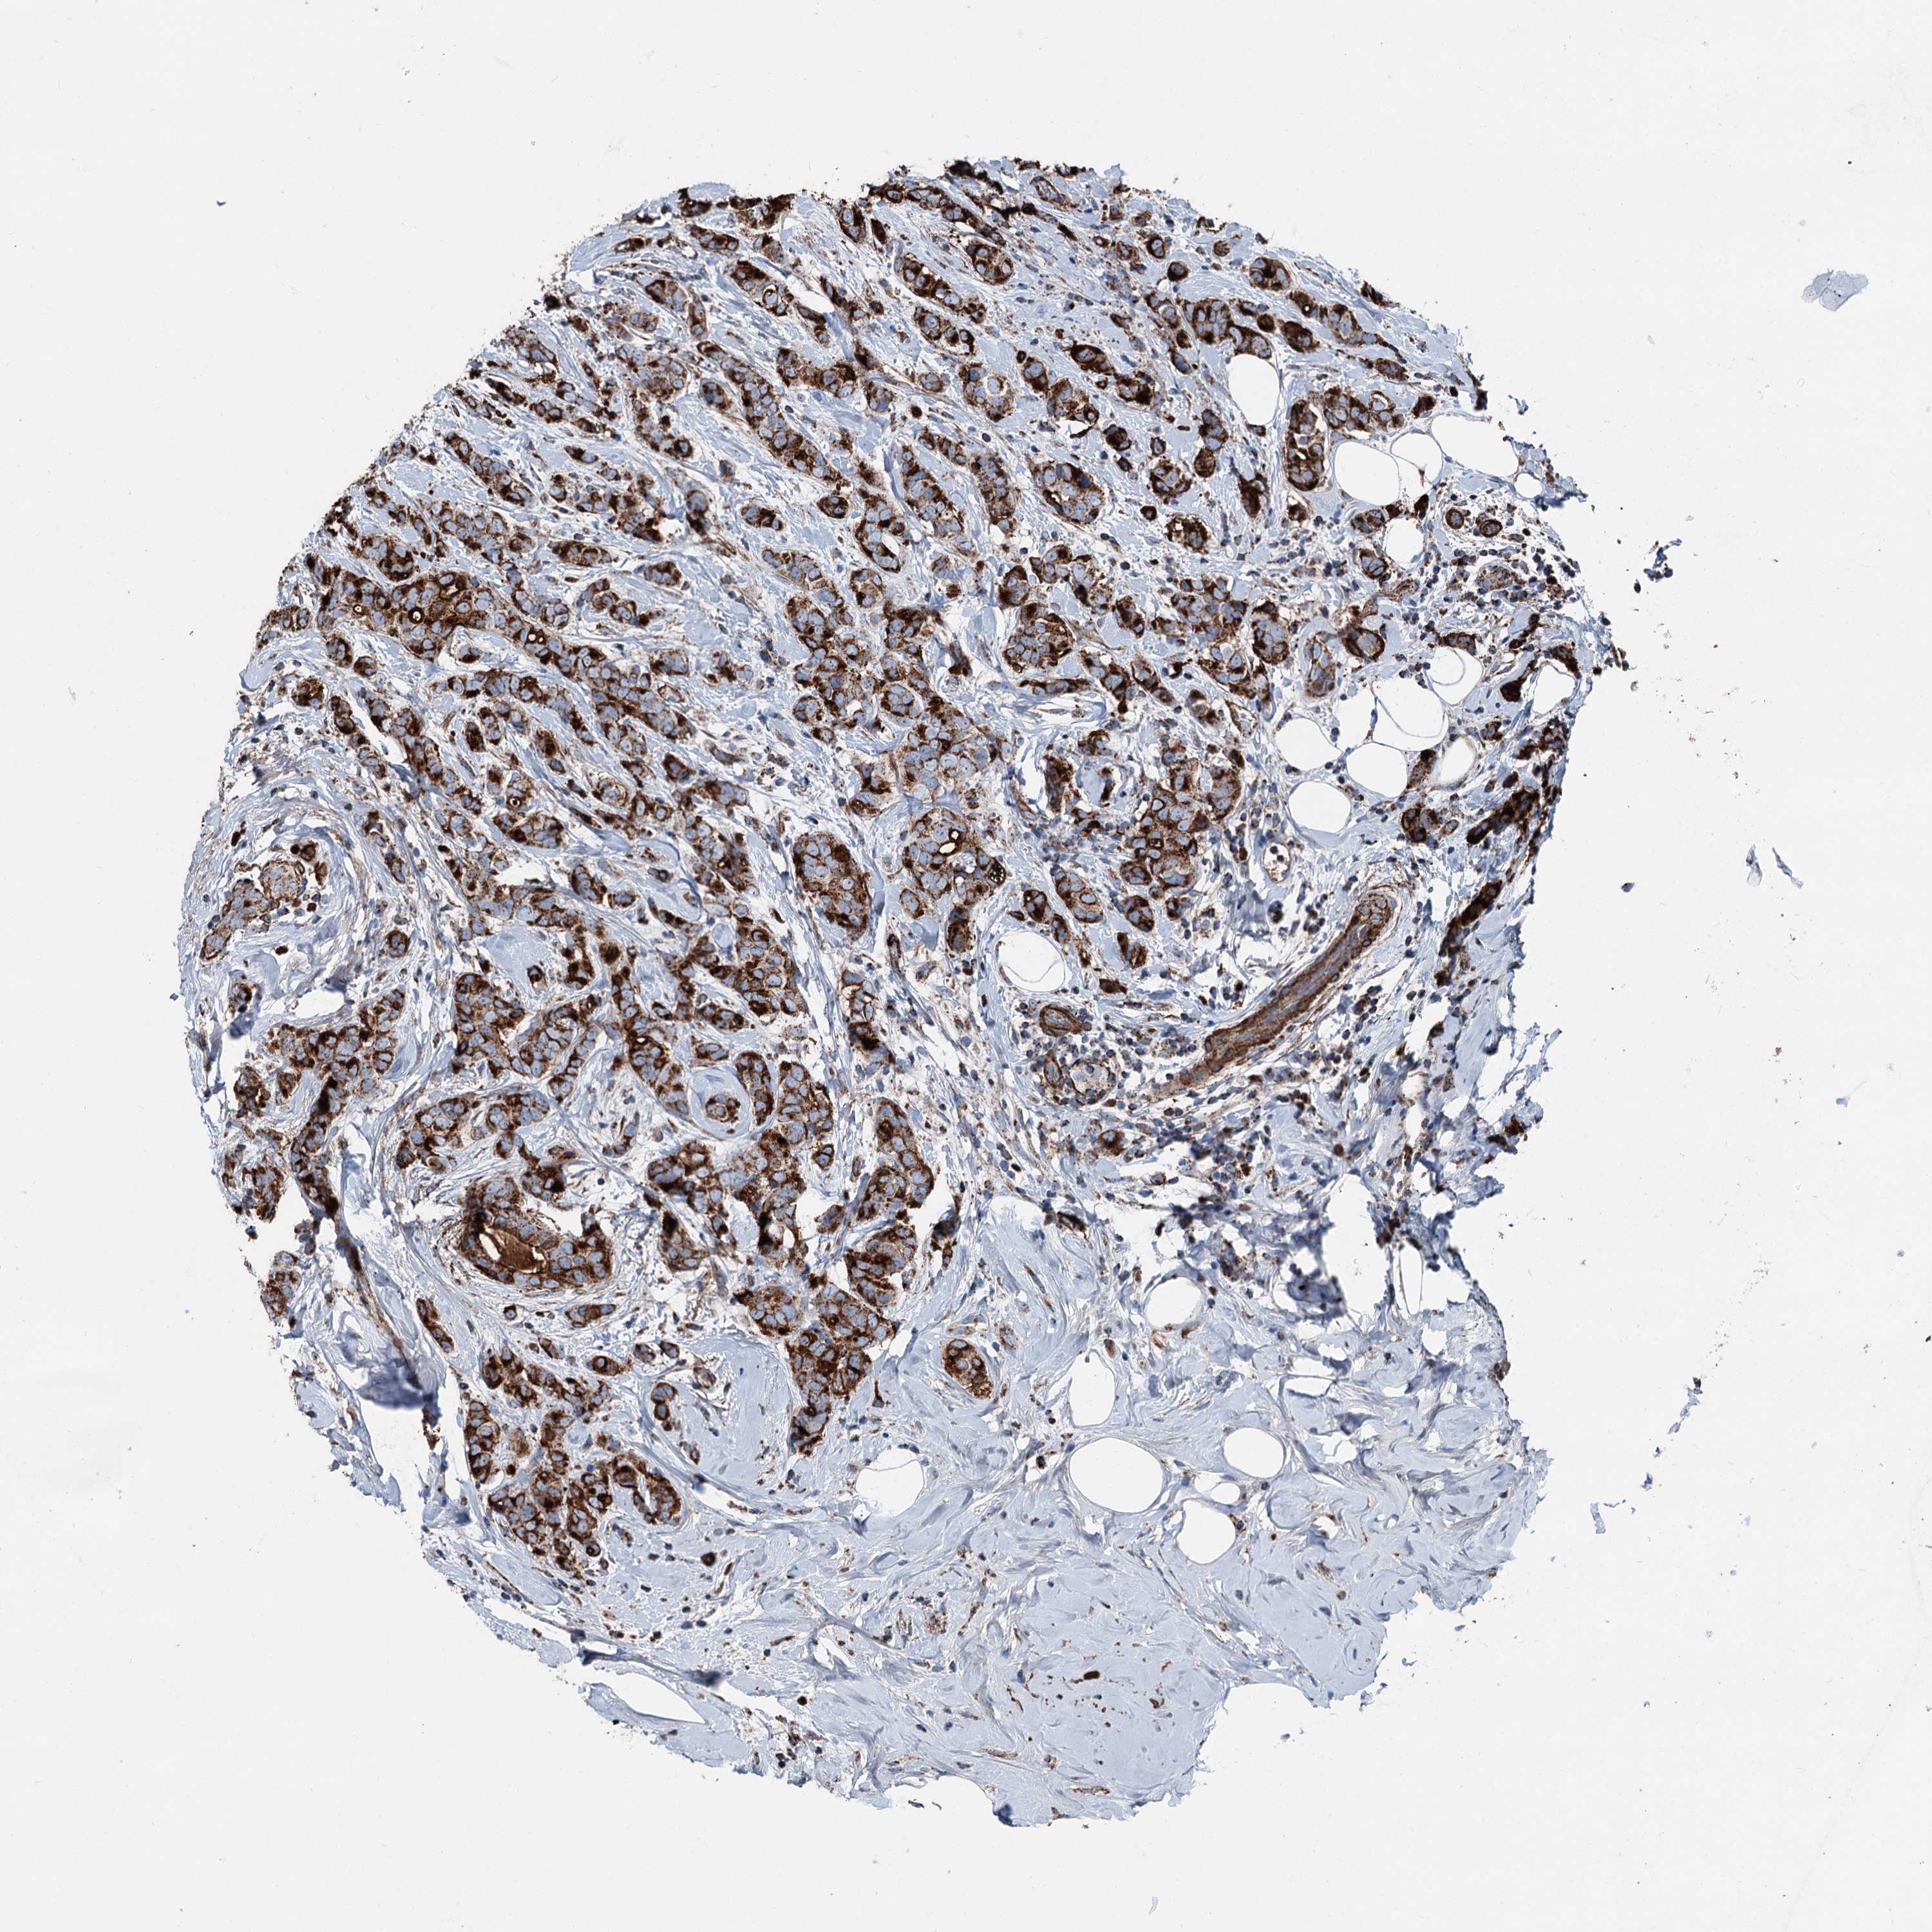

CANCER BREAST CANCER Show tissue menu

BRCA TCGA BRCA VALIDATION PROTEIN EXPRESSION